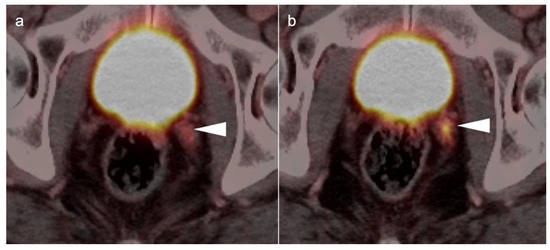

3.5. Penile Cancer